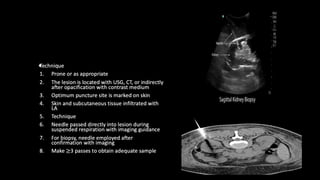

PERCUTANEOUS RENAL BIOPSY

Indication

• Diagnostic biopsy: unexplained renal failure, mass

Contraindication

• Bleeding diathesis

Equipment

• USG or CT guidance

• Bard gun with core biopsy needle

Patient preparation

• Fasting for 4 hours

• Blood parameters

• Premedication/sedation as required

•

Complications

• Bleeding

• Arteriovenous fistula

• Pseudoaneurysm